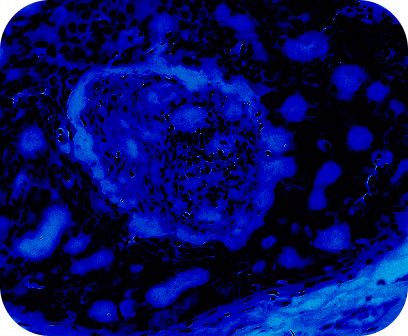

La constante augmentation des troubles anxieux et dépressifs représente un défi majeur, alors qu'ils touchent aujourd'hui plus de 300 millions de personnes dans le monde. Comprendre les facteurs environnementaux et nutritionnels qui influencent l’axe microbiote-intestin-cerveau est donc un enjeu crucial.

Le projet Explore « Microbiote sous influence : l’alimentation moderne à la croisée de la santé mentale » réunit les expertises d’une équipe dédiée à l’étude du microbiote intestinal et de la nutrition et celles de chercheurs spécialisés en neurosciences, tests comportementaux, analyses spatiales du cerveau et approches métabolomiques.

Il a pour objectif d’étudier les altérations du microbiote intestinal, induites notamment par la consommation croissante de produits ultra-transformés. Ces derniers sont en effet reconnus comme un facteur de risque majeur pour la santé humaine, entraînant des conséquences néfastes sur la cognition et étant à l’origine de stress et d’anxiété.